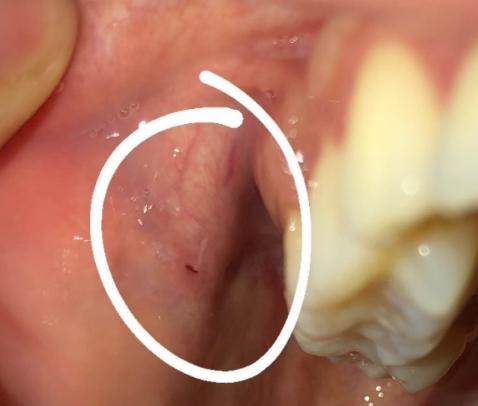

Chào bác sĩ. Em bị vết như này ở hai bên má trong, không đau, không sưng, không sốt. Tuy nhiên vết này giống như một cái lỗ. Em không biết bị từ bao giờ, nhưng từ lúc em biết tới nay là 3 tháng và nó không lành.

Nhìn hình ảnh này thì bác sĩ không thể phân định được vệt đen trên niêm mạc má của em có phải là 1 cái lỗ không hay, phải dùng dụng cụ kiểm tra mới biết được. Vì em cũng có những vết tương tự ở bên má trong, bác sĩ cần khám trực tiếp toàn bộ niêm mạc vùng miệng và hầu họng, đánh giá tình trạng răng lợi hiện tại, với dụng cụ chuyên dụng sẽ giúp xác định được chính xác hơn các sang thương này là gì và cần điều trị ra sao.

Về vấn đề này em khám tại chuyên khoa răng hàm mặt (không phải nha khoa đơn thuần), em nhé.